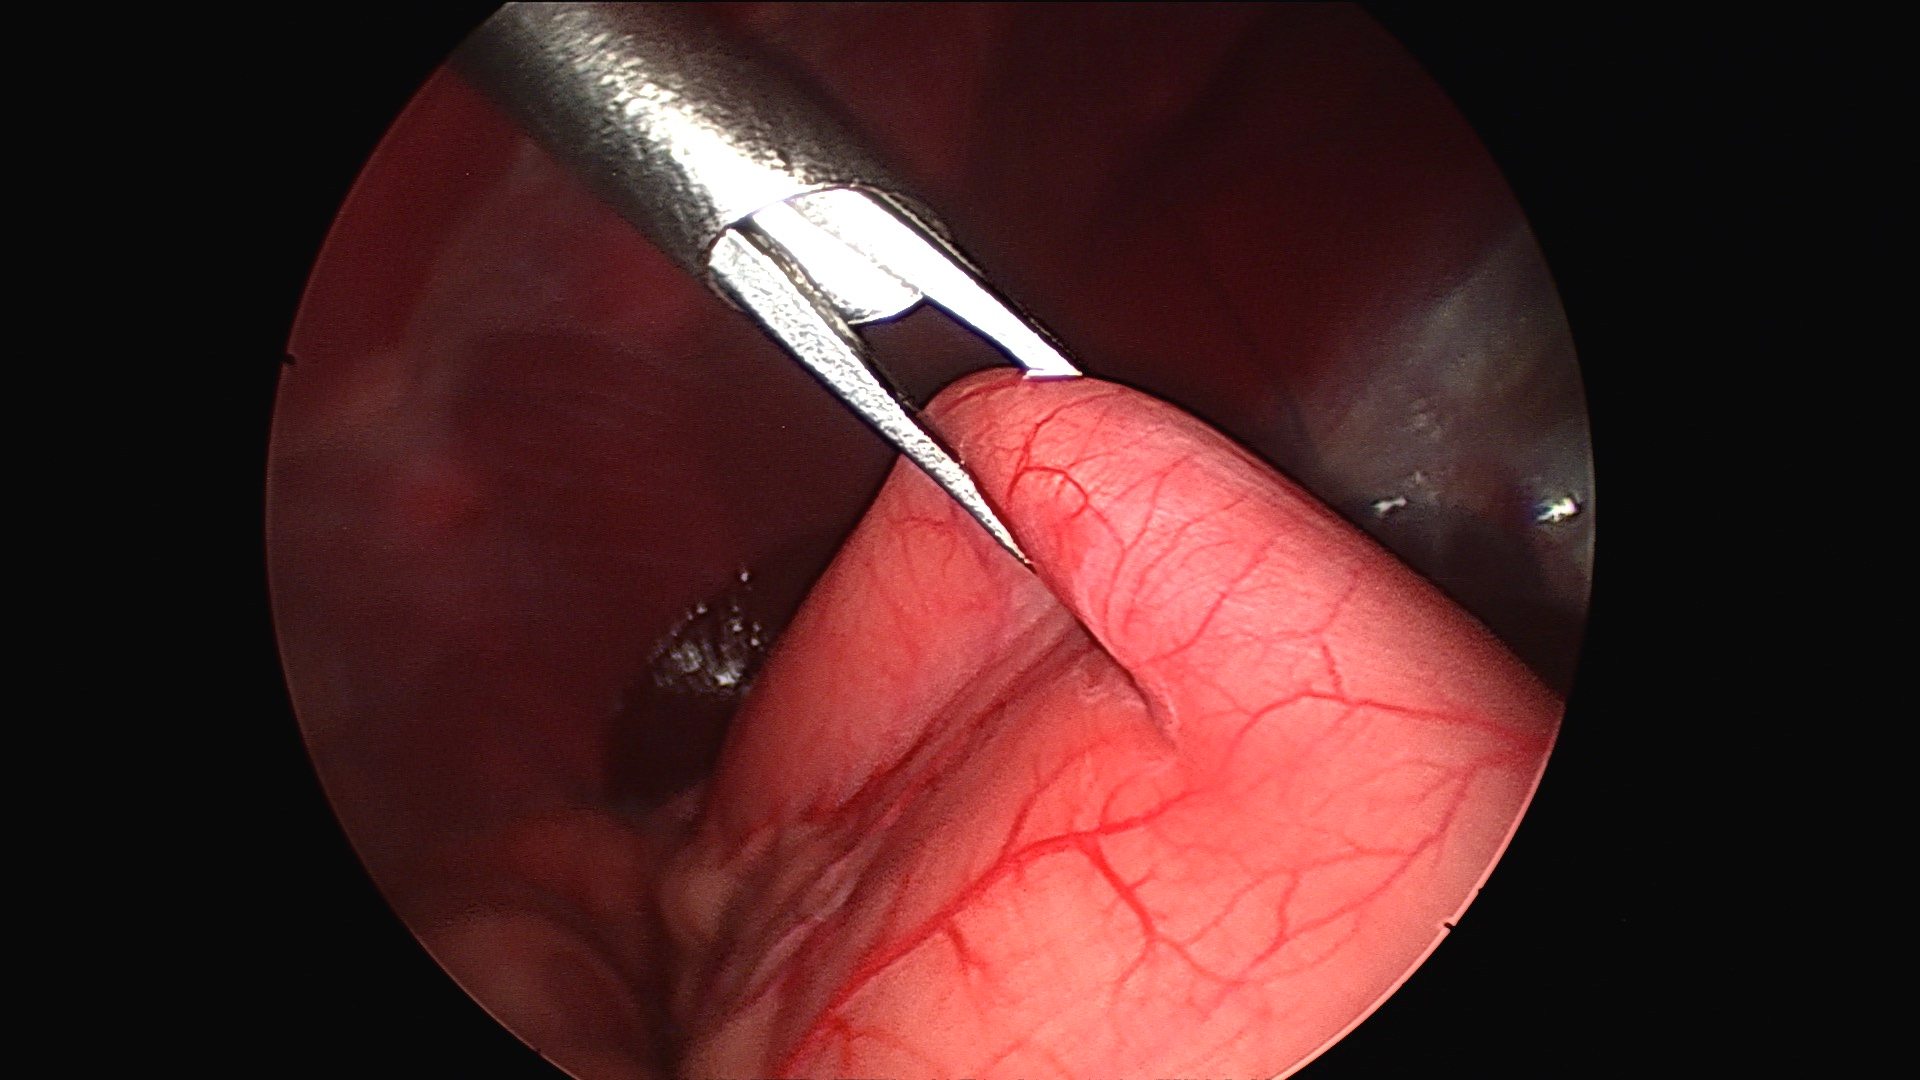

Final appearance of the stomach sutured to the body wall to prevent twisting just prior to the gas being removed from the abdomen (to remove the tension)